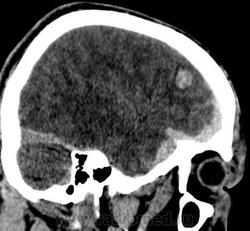

Кт головного мозга, травма.

Молодой человек 24 лет, вчера избит. Поступил в сознании, оринтирован, заторможен несколько.

Уважаемые коллеги, как Вы считаете: помимо всего прочего, имеет ли место субдуральная гематома в передне-медиальном отделе средней черепной ямки справа или это проявление субарахноидального кровоизляиния? Мнения наших экспертов разошлись)). Спасибо!

Я думаю, это ЭПИдуральная гематома. Перелома там точно нет?

По моему присутствует контузионный очаг в лобной доле справа, субдуральная гематома и САК.

Заодно и перелом затылочной кости слева.

Когда парня били, он упал и ударился затылком. Кроме линейного перелома затылочной кости слева, других переломов нет, искала очень тщательно.

Спасибо за мнения! Выставила ушибы лобной и височной доли справа, плащевидную субдуральную гематому лобно-теменно-височной области до 3 мм толщиной с переходом на основание черепа, где в передне-медиальном отделе ср.черепной ямки гематома до 10 мм толщиной, + САК; периорбитальные ушибы мягких тканей. Пока нейрохирурги приняли решение вести пациента консервативно.